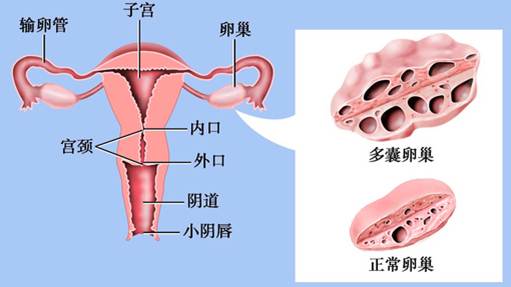

多囊卵巢综合征卵巢和正常卵巢示意图

1.卵巢变化 大体检查:双侧卵巢均匀性增大,为正常妇女的2~5倍,呈灰白色,包膜增厚、坚韧。切面见卵巢白膜均匀性增厚,较正常厚2~4倍,白膜下可见大小不等、≥12个囊性卵泡,直径在2~9mm。镜下见白膜增厚、硬化,皮质表层纤维化,细胞少,血管显著存在。白膜下见多个不成熟阶段呈囊性扩张的卵泡及闭锁卵泡,无成熟卵泡生成及排卵迹象。